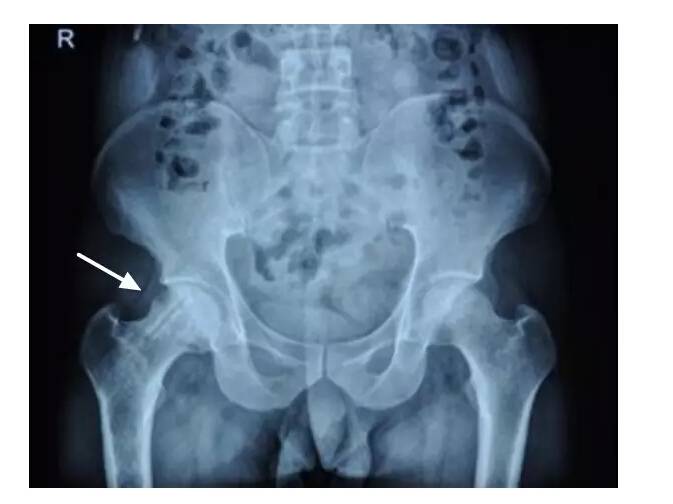

IV期X线片显示股骨头变扁